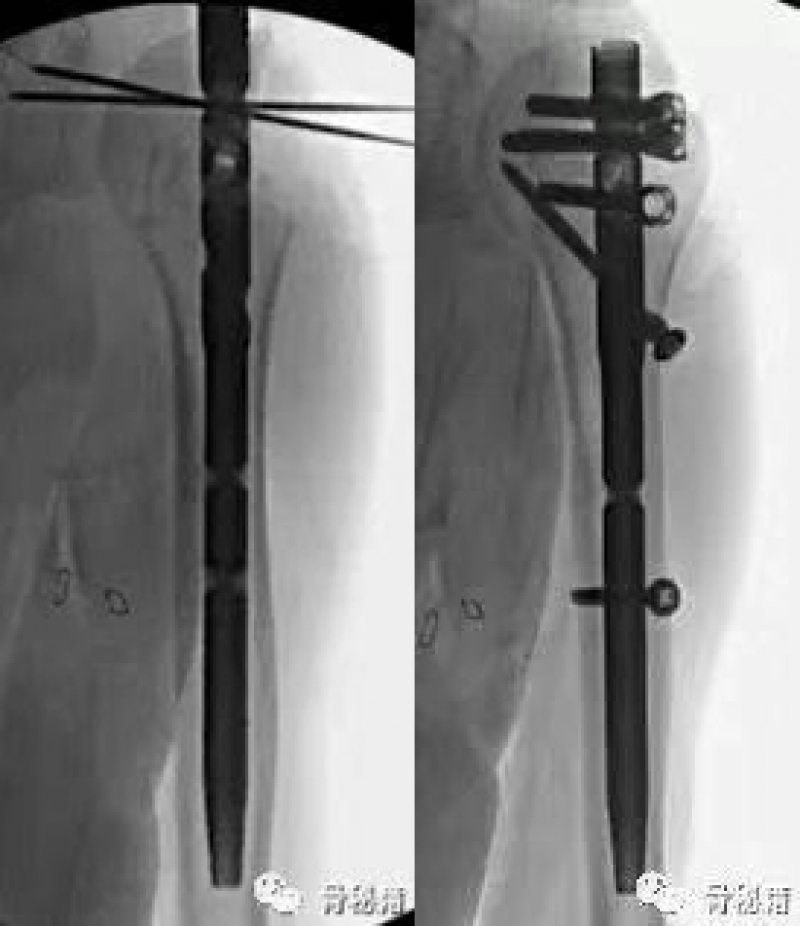

这是一个我们常见的肱骨近端骨折,我们可以看到外侧的大结节粉碎

中间有很多头内的缺损,常见的固定是将外侧复位之后通过钢板在外侧对剩余的头进行固定,这种偏心的固定在骨缺损的情况下通常很容易失败。

而我们应用髓内钉就是另外一种情况,通过头上较好骨质对主钉的把持来维持整个固定,这个病例为了很好的控制头的固定,使得进针点非常靠内,这样才能把持主头的骨折块,通过主钉来重建生物力学的稳定性,再通过锁定来重建大结节的部位,相对来说失败的几率更小一些

在复位好的基础上,植入合适的主钉导针

导针一旦植入,这个手术就完成了一半了

剩下就按照步骤进行